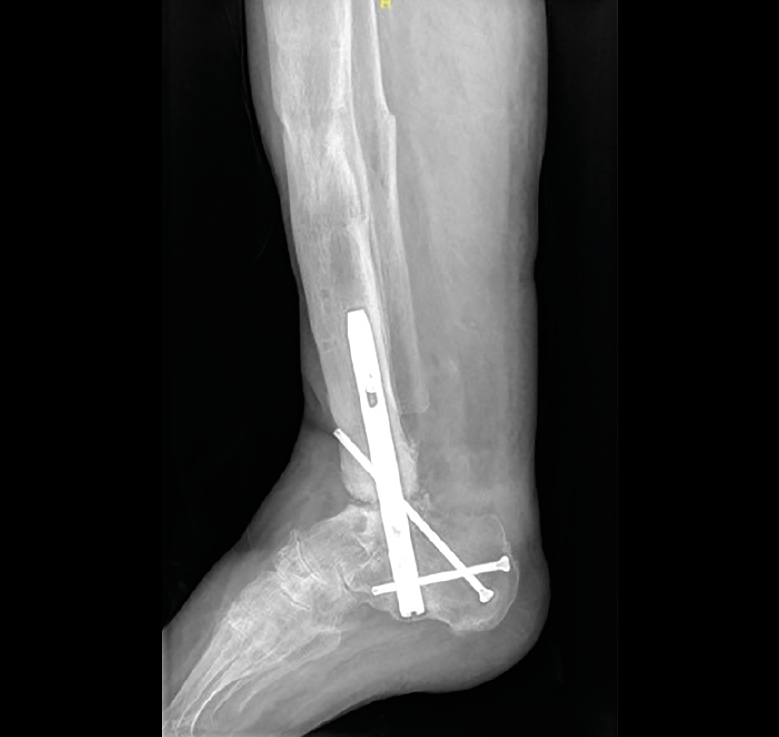

El paciente con antecedente de fractura de pilón tibial presentaba una pseudoartrosis del foco de fractura metafisario con antecedentes de infección de la osteosíntesis previa. Optamos, una vez tratada y curada la infección, por el clavo retrógrado como método de tratamiento de ambas lesiones, la pseudoartrosis de la fractura y la degeneración articular grave. Aunque se consiguió la consolidación del foco de fractura y la fusión de la articulación subtalar, la artrodesis del tobillo no se consiguió. No precisaba ayuda para la marcha y el dolor mejoró de 8 a 2 al año de evolución (Figura 1).

Figura 1. Radiografía del caso 3 con ausencia de consolidación de la articulación tibiotalar.